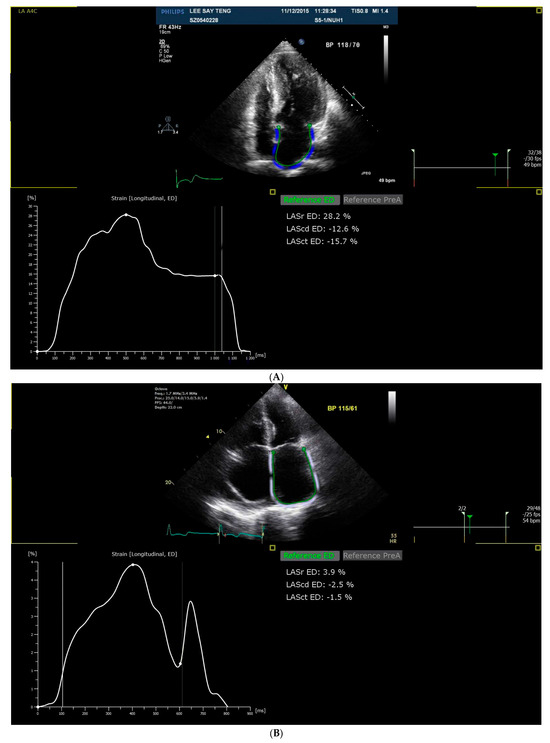

2.4. Strain Analysis

| LASr | Left atrial reservoir strain |

| LAScd | Left atrial conduit strain |

| LASct | Left atrial contraction strain |